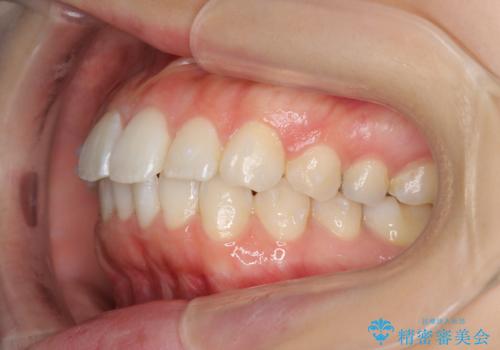

前歯のがたつき インビザラインで

治療症例の内容

- 前歯のがたつきを治したいとのことでした。歯を抜かずにできる範囲で引っ込めたいとのことでした。

歯列の側方拡大(横に広げる)と、エナメル質の削合で並べました。

歯を抜いているわけではないので、口元はそこまで変化はありませんが、前に出すことなくデコボコは取れたと思います。